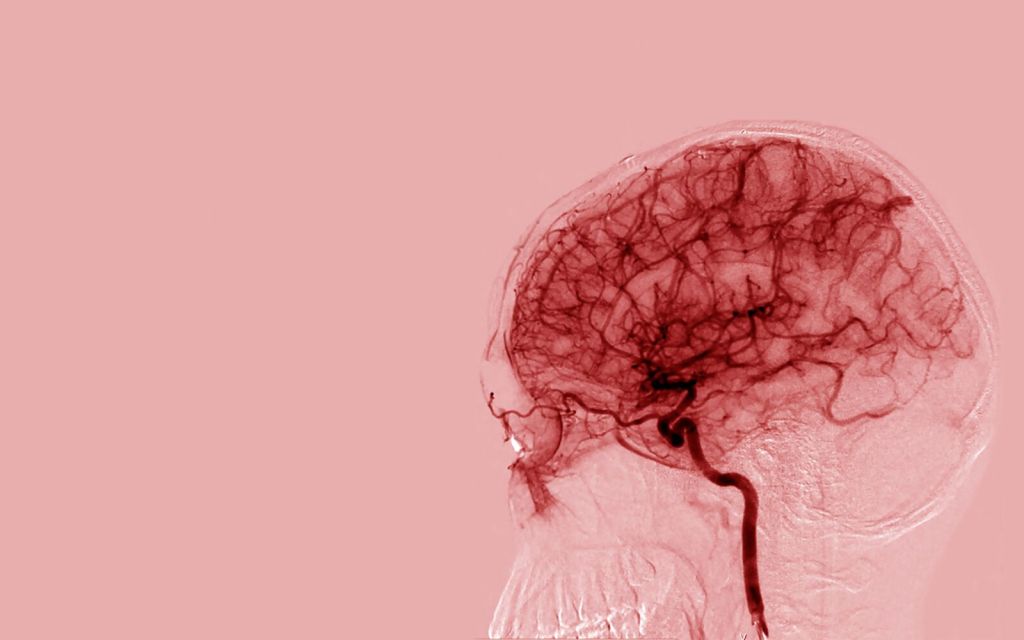

At 2.00 after brain scans and radiography accessed by wheelchair, Joe decided to keep me overnight where I was monitored throughout and woken hourly. He suggested that I had some narrowing of two access points of blood to the brain, probably narrow from birth. As I aged, the blood pushed a bit harder to get round, and the blood pressure went up. The medicine prescribed to suppress the blood pressure confused the body – hence TIA (transient ischaemic attack).